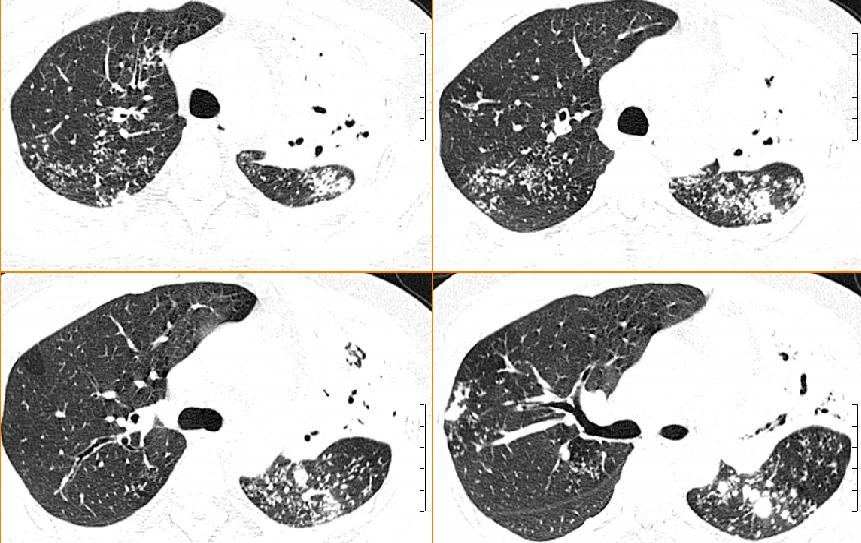

女,33岁,咳嗽5月。

左肺上叶前段致密,内见空气支气管征,相应部位胸膜增厚粘连,双肺上其他肺叶不同程度斑片状播散病灶,结合咳嗽5月的病史,考虑:双肺上叶继发性肺结核。

双上肺、左下肺背段肺结核,左上肺膨胀不全.

支持双上肺结核(左肺上叶干酪性肺炎)。

左肺上叶前段致密,内见空气支气管征,相应部位胸膜增厚粘连,双肺上其他肺叶不同程度斑片状播散病灶,结合咳嗽5月的病史,考虑:双肺上叶继发性肺结核伴左肺上叶肺含气不良。